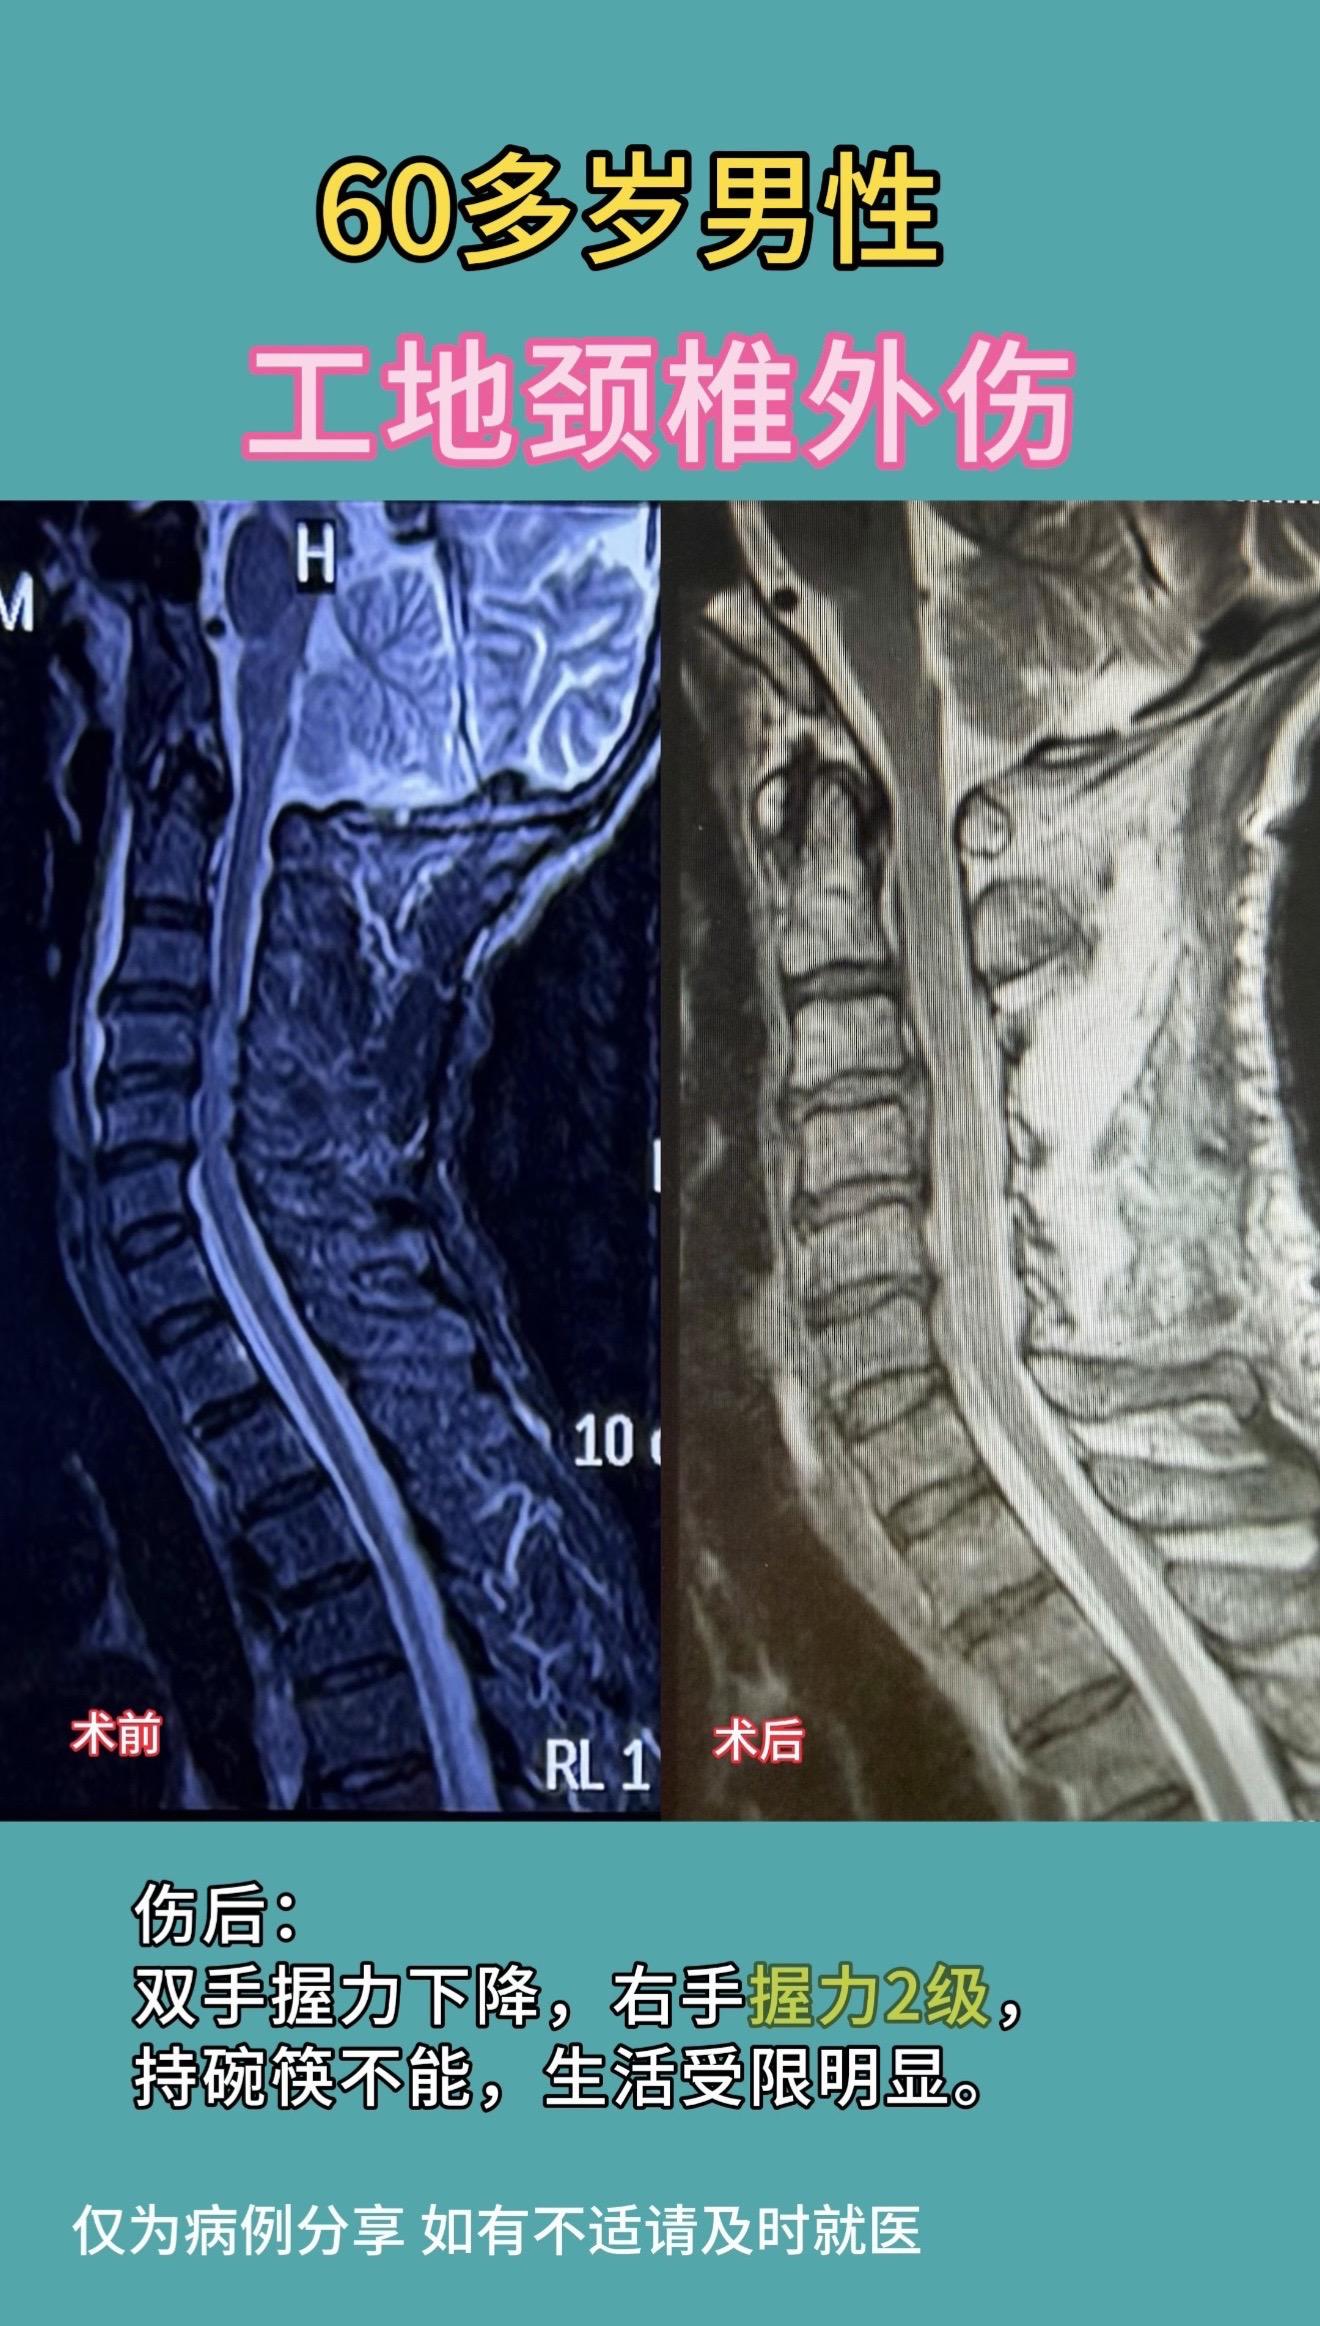

60多岁男性,工地颈椎外伤,伤后双手握力下降,右手握力2级,持碗筷不能...